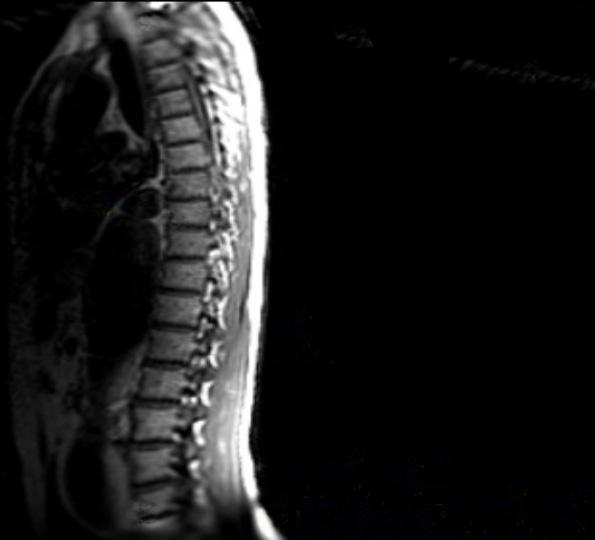

Preventing spinal cord ischemia:

Novel techniques for direct segmental artery revascularization show promise, WVS hears

A vascular surgery team from the University of Southern California (USC) demonstrated the feasibility of direct revascularization of segmental arteries to prevent spinal cord ischemia (SCI) using novel endovascular or extraanatomic bypass techniques in high-risk patients with complex thoracoabdominal aortic aneurysms (TAAAs).

This followed a retrospective review of fenestrated or branched endovascular aneurysm repairs (F/BEVARs) over a five-year period, attendees of the recent Western Vascular Society (WVS) annual meeting (Sept. 9–12) were told. The early work, which involves 12 patients undergoing either an endovascular or open approach, was hailed by audience member Benjamin W. Starnes, MD, chief of vascular surgery at University of Washington Medicine in Seattle, who said, “This is a new idea. I applaud the courageousness of our colleagues at USC for pursuing this.”

U SC integrated vascular surgery resident Anand Ganapathy, MD, who presented the study results, told WVS 2023, held in Koloa, Hawaii, that nine patients were treated endovascularly,

See page 4

FROM THE COVER: PREVENTING SPINAL CORD ISCHEMIA: NOVEL TECHNIQUES FOR DIRECT SEGMENTAL ARTERY REVASCULARIZATION SHOW PROMISE

with a total of 11 segmental arteries incorporated. Ganapathy outlined how seven were revascularized using a directional cuff sewn directly onto a physician-modified graft that was extended with self-expanding Viabahn stents; two of the arteries were treated using stented fenestrations; and the remaining two—located along the seal zone—were tackled using unbridged, large fenestrations without covered branched stents. The other three patients received an extra-anatomic bypass.

Extents I and II were the most common type of TAAA among the patient group, Ganapathy continued. Procedural details for endovascular repair of the aneurysms demonstrated an average of 4.3 target vessels (2–6) treated, with a technical success rate of 83%.

Failures (two patients) involved a bridging stent to a renal artery “that was dislocated from the fenestration and not recoverable” and a malalignment of an unstented fenestration to an intercostal artery “maintained with an uncovered stent.”

Nine patients had successful prophylactic spinal drain placement. The three patients who underwent open repair of their segmental arteries received their bypass an average of three days prior to the F/BEVAR procedure.

Ganapathy reported no mortality at 30 days post-procedure. Two patients—one who had a staged extra-anatomic bypass, the other an unstented fenestration—incurred spinal cord ischemia that “resolved completely by discharge.” Both had prophylactic spinal drain placement.

Average follow-up was 472 days. Three of the 14 targeted segmental arteries occluded during follow-up, Ganapathy added. Occluded branches involved one extra-anatomic bypass and two directional cuffs. “They occurred beyond one year without causing spinal cord ischemia,” he said.

G anapathy concluded: “Spinal cord ischemia remains a serious complication of F/BEVAR, despite current mitigation strategies. Our initial experience demonstrates feasibility of endovascular and ex-

“Our vision is that someday this might serve as another adjunct to the current spinal cord ischemia mitigation protocols”

ANAND GANAPATHY

continued from page 1

tra-anatomic bypass for segmental revascularization in select patients.

“Further work is planned to improve patient selection through anatomic and dynamic assessment of spinal cord perfusion patterns, as well as the safety and efficacy of segmental artery revascularization procedures through a multidisciplinary, collaborative effort across expertise from a growing list of specialists. Our vision is that someday this might serve as another adjunct to the current spinal cord ischemia mitigation protocols.”

zones that are much more extensive than open repairs. Additionally, during open repairs we can reimplant intercostals. This cannot be done during stent graft [implantation], hence intercostal revascularization may not be the holy grail in the prevention of paraplegia.”

K arthikeshwar Kasirajan, MD, a clinical professor of vascular surgery at Stanford University, the designated discussant of the paper at WVS, summarized the study’s headline findings, outlining how the novel techniques had been employed in 3.8% of F/ BEVAR patients reviewed during the study period. Some 11% of the endovascular group and 33% of the open group developed transient paraplegia, he said.

Kasirajan commented: “In my opinion, it should be noted that stent grafts have a lower instance of paraplegia when compared to open repairs in general. This is despite the fact that length of coverage is often more extensive as to require landing

Alan Lumsden, MD, chair of the Department of Cardiovascular Surgery at Houston Methodist in Houston, Texas, congratulated the USC team on the ground-breaking nature of their work, asking Ganapathy and colleagues to drill down on any guidelines they follow to determine which patients should receive the novel approach.

Senior author of the study, Sukgu Han, MD, co-director of the Comprehensive Aortic Center at USC’s Keck Hospital, said: “Patient selection is everything. There’s probably more value from putting this protocol together with people from different specialties, maybe actually in the characterization of the spinal perfusion and individual variability.

“Because, so far, really the only surrogate marker we are looking at, in really very few select patients, is the size and assumption that that carries dominant collateral to the spinal cord.”